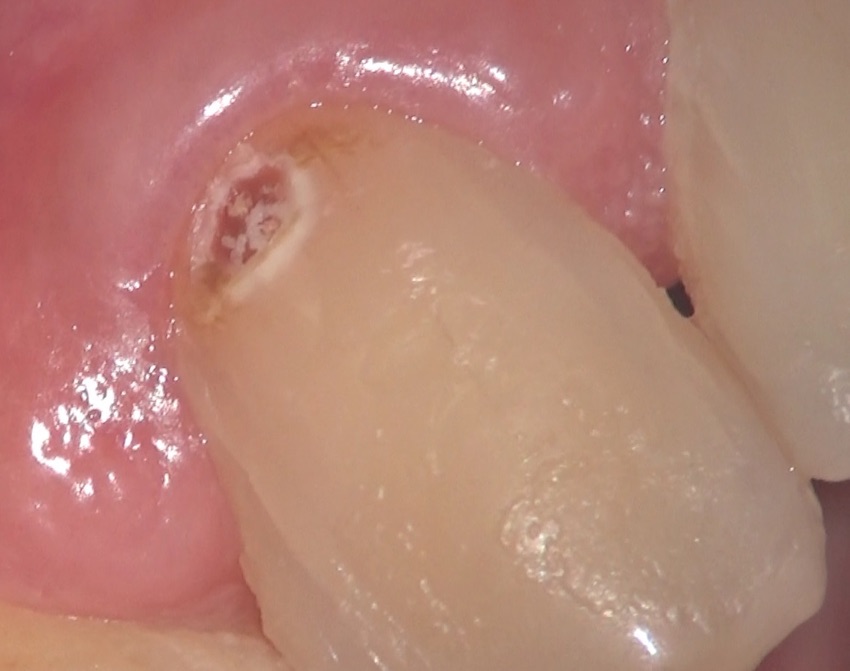

術前の状態です。歯茎のキワに、茶色い部分があるのがわかると思います。これが虫歯です。

これを、マイクロスコープを用いて、取り除きます。